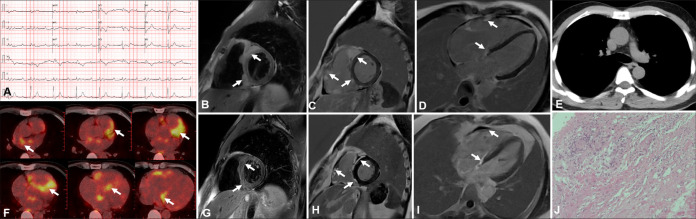

Cardiac sarcoidosis (CS) represents a rare yet potentially life-threatening condition characterized by non-specific clinical symptoms that maybe easily missed by clinicians. In this case series, the clinical presentations, various imaging modalities' characteristics, and the management of four patients, each with distinct phenotypes of CS confirmed through endomyocardial biopsy, are discussed. Advanced imaging techniques, including positron emission tomography, revealed the focal septal uptake of 18F fluorodeoxyglucose, which suggests an ongoing inflammation, whereas contrast-enhanced cardiac magnetic resonance demonstrates septal late gadolinium enhancement, which indicates replacement fibrosis. These features of multimodality imaging in CS can assist in patient diagnosis and treatment.